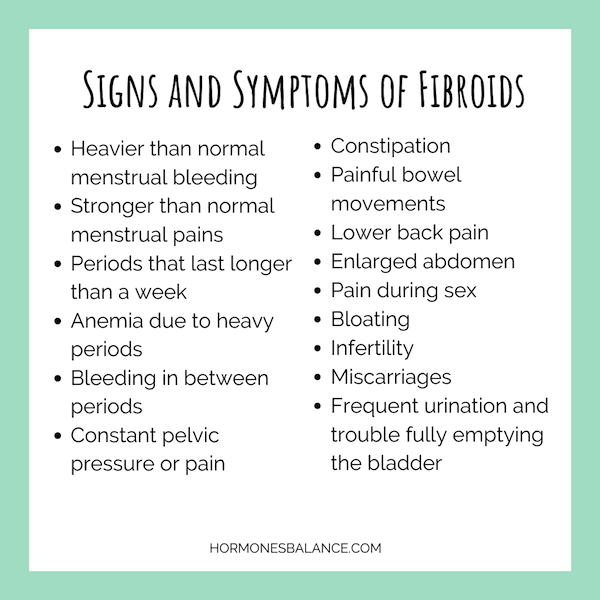

What are the symptoms of uterine fibroids?

What are the Symptoms of Fibroids? – Best Acupuncture Hamilton NZ

[31+] Uterine Fibroids Signs And Symptoms

5 IMPORTANT SYMPTOMS OF FIBROID – Go Viral Malaysia

Uterine Fibroids Symptoms and Risk Factors You Should be Aware About

SYMPTOMS OF UTERINE FIBROIDS